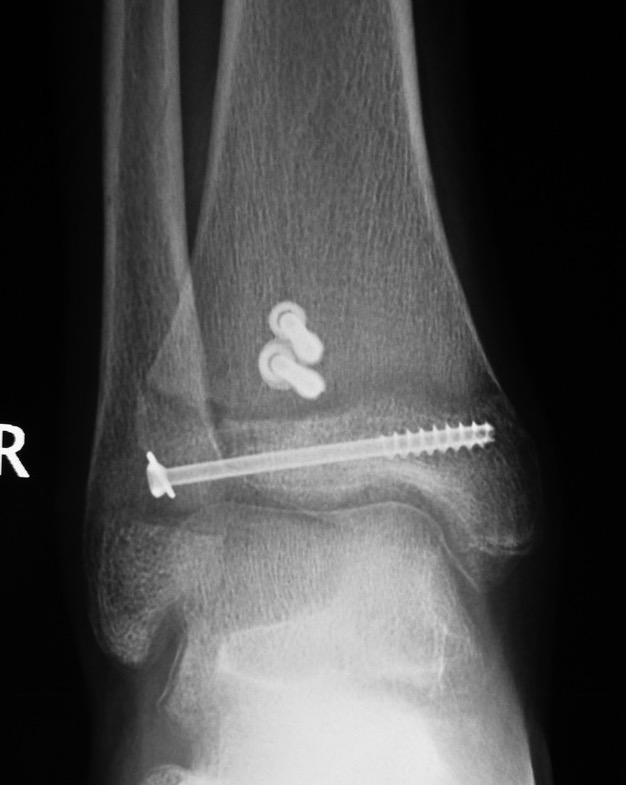

Operative management

Indication

Displaced articular fracture > 2 mm

Technique

AO surgery reference triplanar fixation

JBJS Essential surgical technique triplanar fixation video

Anterior approach between EHL and EDL

- reduce fracture with large reduction forceps

- epiphyseal screw from lateral to medial / medial to lateral

- metaphyseal AP screw into Thurston-Holland fragment

Results

- systematic review of 830 adolescent triplanar fractures

- average age 13

- 17% associated fibular fractures

- premature growth closure / leg length discrepancy 1%